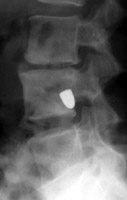

Tumbling Bullet Sign

Post traumatic bone cyst

Two sets of frontal and lateral radiographs, separated only by time, which reveal the "tumbling bullet sign"--which is simply a bullet which changes its location and orientation within a solitary bone cyst. This sign serves two purposes. It is documentation of the evolution of a solitary bone cyst as a corollary of trauma, and reveals the free movement of the foreign body within the confines of the lesion establishing its cystic rather than solid nature. It is similar to the fallen fragment sign.

- Click on the image for a larger versionA - Click on the image for a larger versionB - Click on the image for a larger versionC - Click on the image for a larger versionD

bulletTaxin RN, Feldman R.: The tumbling bullet sign in a post-traumatic bone cyst. Am J Roentgenol Radium Ther Nucl Med 1975 Jan;123(1):140-3.          [See related articles]